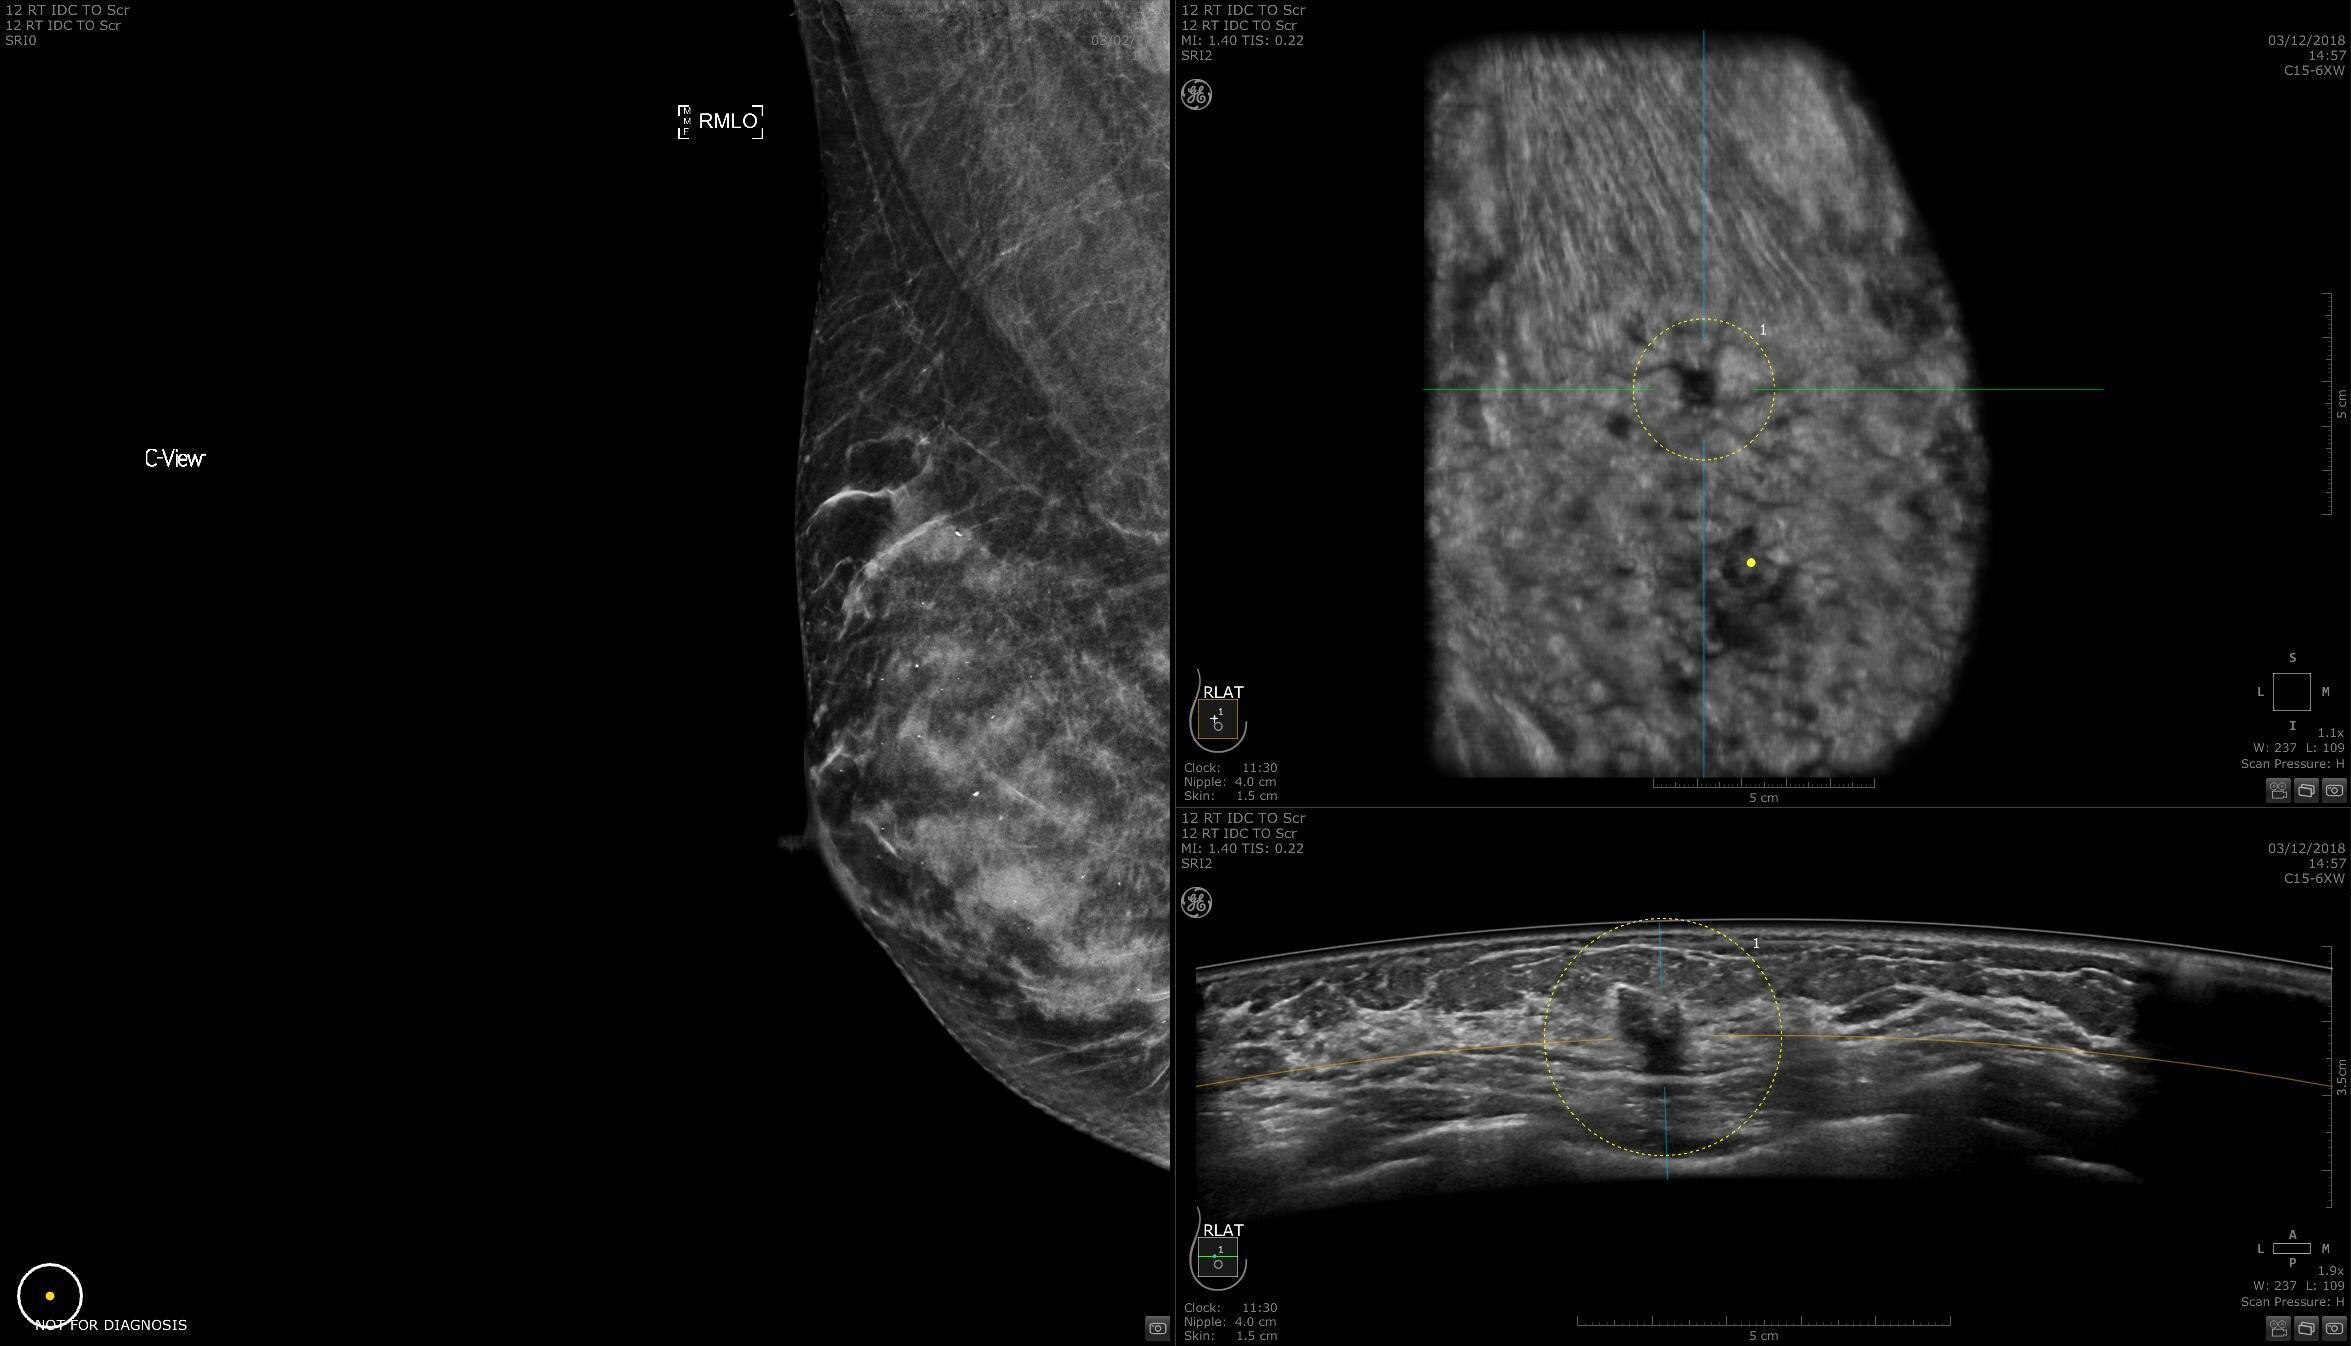

TREATMENT

Smart surgical planning

Invenia ABUS 2.0 provides a full view of the breast, depicting the extent of the lesion, multiplicity and potential stromal involvement, helping to achieve a better surgical approach.